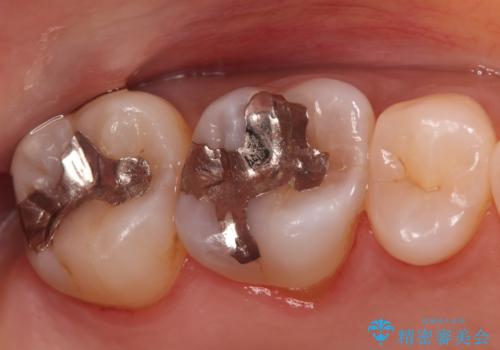

銀歯の下の虫歯|オールセラミッククラウン

担当医 河野豊嘉

奥歯に虫歯があると言われた セラミッククラウンでキレイで長持ちする歯へ

担当医 榊原康平